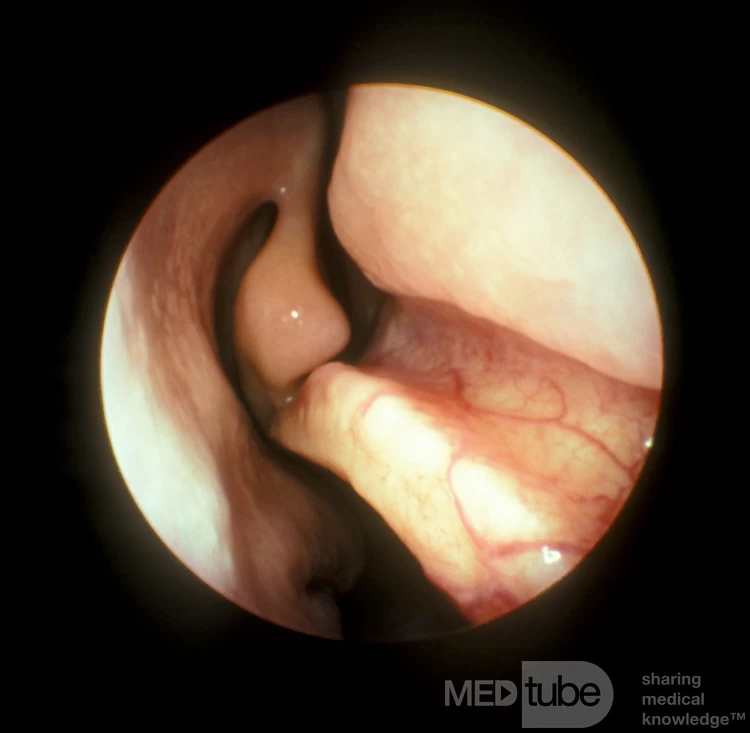

Trong khi vách ngăn mũi "lý tưởng" nằm ở đường giữa của khoang mũi, hầu hết các vách ngăn mũi bình thường đều lệch một chút so với đường giữa. Những độ lệch tối thiểu như vậy thường không ảnh hưởng đến luồng không khí qua mũi và không nên được coi là bất thường. Độ lệch vách ngăn mũi đủ nghiêm trọng để ảnh hưởng đến luồng không khí qua mũi là tương đối phổ biến và thường liên quan đến nửa trước của vách ngăn mũi [sụn tứ giác].